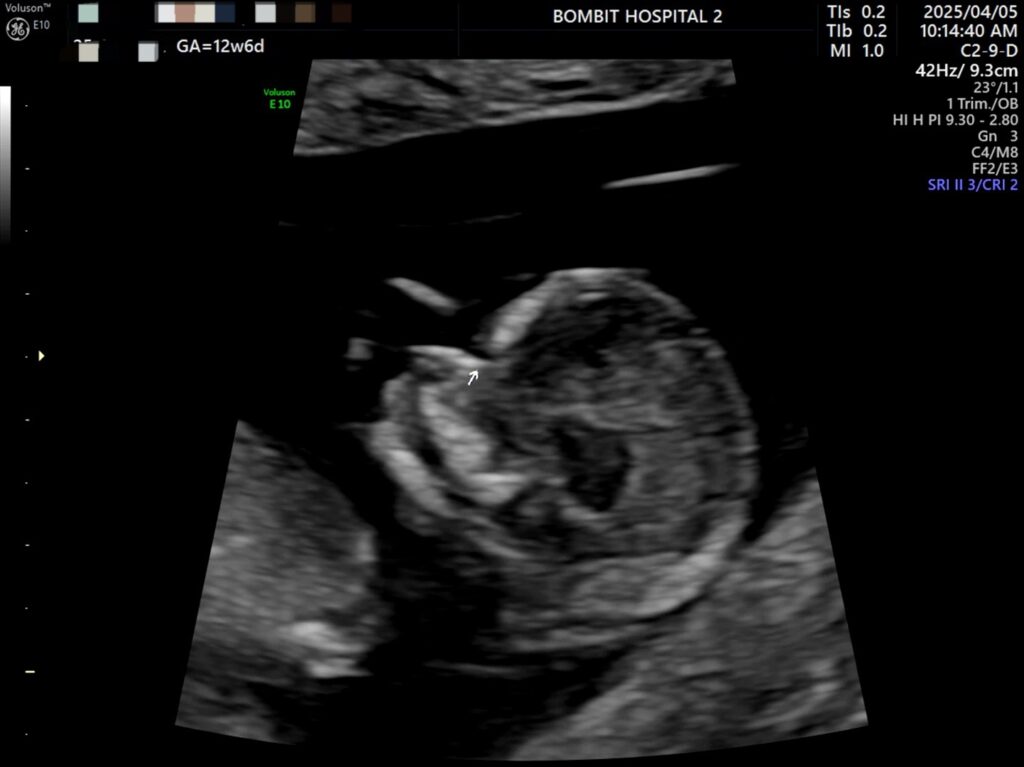

봄빛병원에 다시 방문. 정밀초음파도 하고, 다시 진료도 보았다.

정밀초음파 사진.